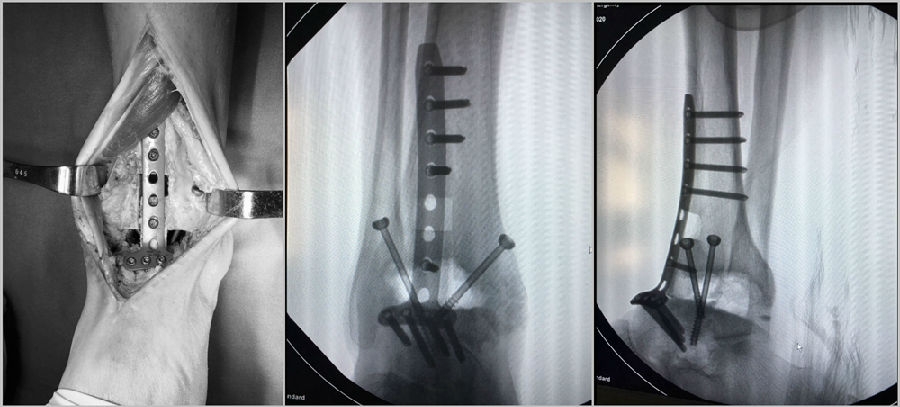

手术中资料

23 手术后资料